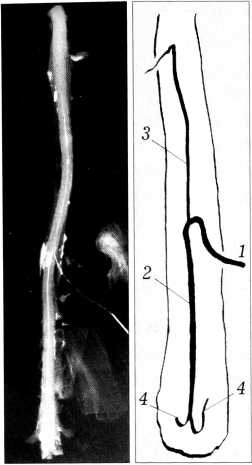

Все исследованные препараты были разделены нами согласно классификации А.А. Скоромца [1- 3], в которой выделяются магистральный тип кровоснабжения передней спинальной артерии (варианты 1,2,3) и рассыпной тип (вариант 4). Магистральный тип, вариант 1 — все сегменты спинного мозга ниже Т2-ТЗ снабжаются одной большой радикуломедуллярной артерией — артерией Адамкевича (рис. 1). Магистральный тип, вариант 2 — помимо артерии Адамкевича, имеется еще одна дополнительная радикуломедуллярная артерия, следующая со вторым поясничным или первым крестцовым корешком. Магистральный тип, вариант 3 — помимо артерии Адамкевича, имеется еще одна артерия, сопровождающая один из грудных корешков (так называемая верхняя дополнительная радикуломедуллярная артерия). Рассыпной тип (вариант 4) — грудопоясничный отдел спинного мозга кровоснабжается тремя и более радикуломедуллярными артериями, из которых одна, с большим, чем все остальные, диаметром является артерией Адамкевича (рис. 2).

Рис. 1. Магистральный тип кровоснабжения спинного мозга. 1 — артерия Адамкевича; 2 — передняя спинальная артерия, нисходящий отдел; 3 — передняя спинальная артерия, восходящий отдел; 4 — задние спинальные артерии.